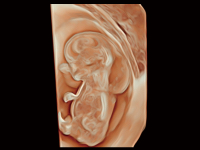

作為開立醫(yī)療全新打造的超高端旗艦超聲產(chǎn)品,從探頭抬起喚醒開啟掃查到多維探頭發(fā)射接收,通過先進(jìn)的場(chǎng)成像發(fā)射、自適應(yīng)聚合重建等技術(shù),基于RF Data原始射頻數(shù)據(jù)在圖像生成、高端功能等方面實(shí)現(xiàn)突破,為婦產(chǎn)科、兒科提供全方位臨床解決方案。

夢(mèng)溪?P80以“關(guān)愛女性”為基石,提供全方位的解決方案,量身定制以滿足女性的健康需求,涵蓋婦科、生殖健康檢查、產(chǎn)前篩查及產(chǎn)后康復(fù)等領(lǐng)域。